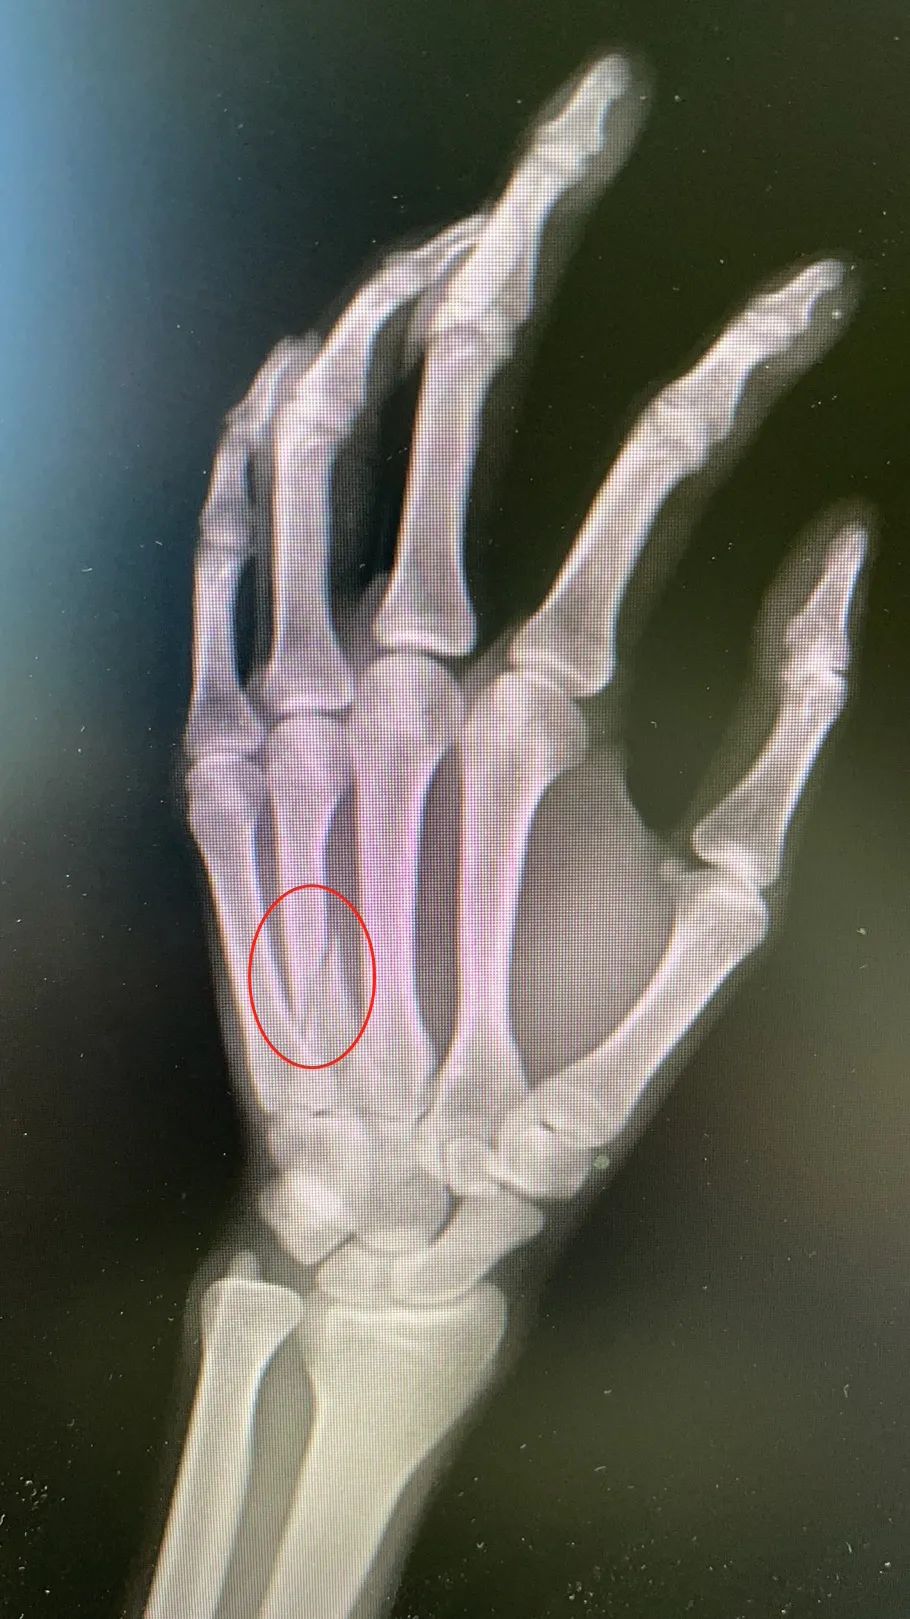

周先生骨折部位。

“右手第四掌骨,有明显的骨折,因为骨部位有旋转移位,需要手术固定。”在武汉市第四医院,手外一科医生陈焱介绍。

陈焱解释,像这种握拳后撞击硬物而导致骨折的,在医学上通常称为“拳击手骨折”,拳击手骨折是一种发生于掌骨的骨折,常发于第4、第5掌骨。

这种骨折很少发生在有拳套保护的职业拳击手身上。而更多见于街头打斗中用“裸拳”打斗的人群。“许多人认为拳头很硬,实际上手部掌骨与身体其他部位骨皮质相比,属于最薄的部位,所以当父亲周先生的拳头打碰到儿子前臂肘关节时,骨皮质较薄的手掌骨会骨折。”